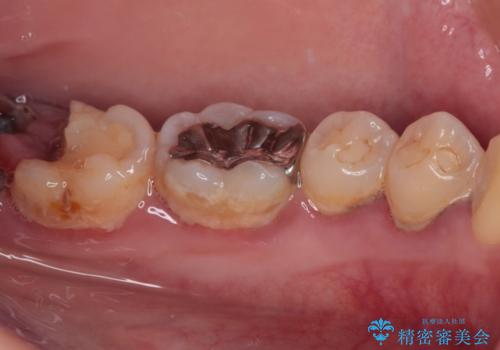

- 過去の歯医者通いの恐怖から虫歯を放置してきたものの、一大決心して来院された患者様です。

神経組織の失活している歯や歯根だけが残っている歯などがあり、全体的に歯石も多く付着している状態でした。

まずは歯石除去とブラッシング方法などの衛生指導を徹底的に行って口腔内環境を改善し、汚れの溜まりやすくなっている親知らずは全て抜去することとしました。

その後、歯根だけとなっている歯はインプラントに、神経組織の失活している歯は根管治療を行い、いずれもオールセラミッククラウンにて補綴治療を行うこととしました。

右上のインプラント治療は、1DAYインプラント治療(抜歯即時埋入・即時荷重)の適応となりましたので、通常3回必要な外科処置の回数を1回に集約させることができました。

口腔内の環境が大きく改善し、現在はご自身のプラークコントロールにより良い状態が維持できるようになりました。